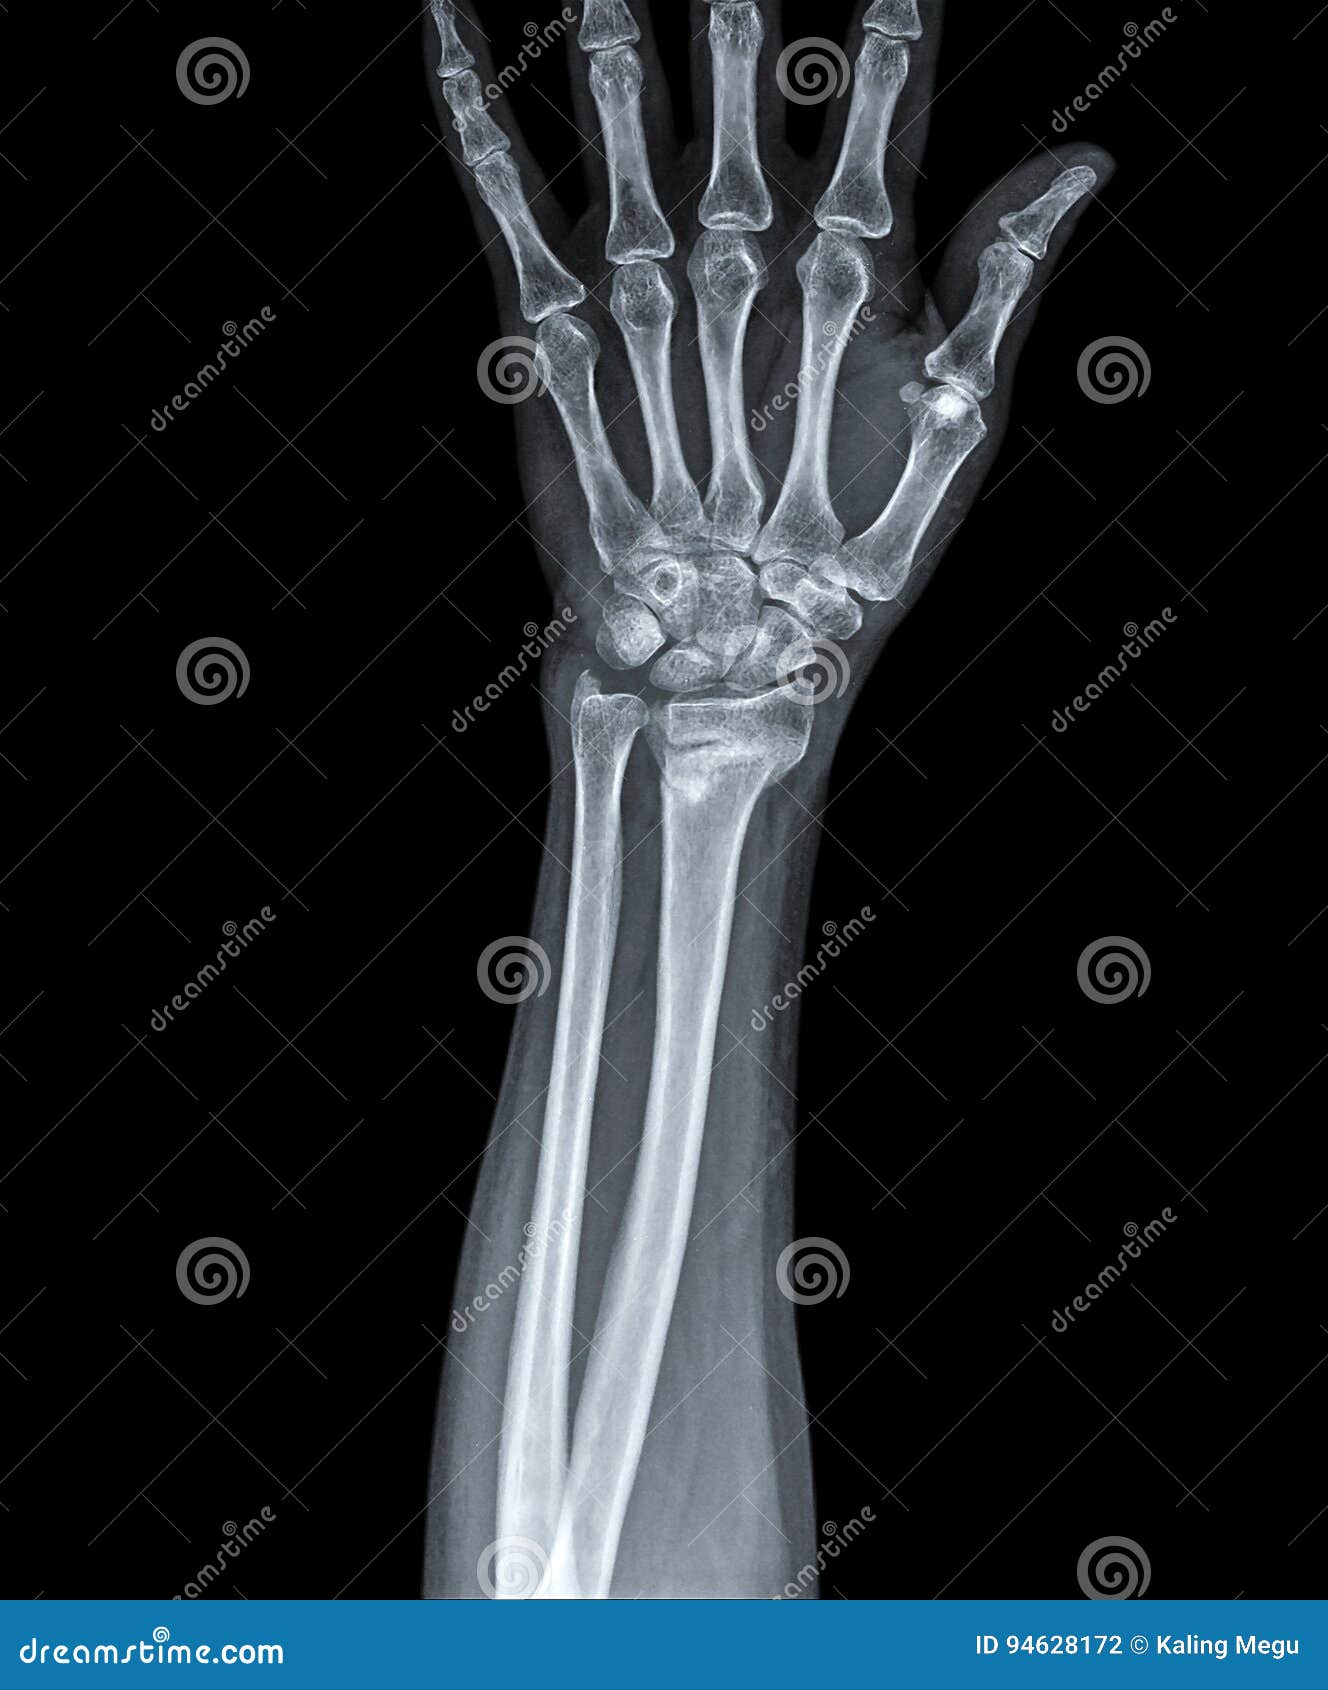

From www.dreamstime.com

X Ray of Hand with Fracture Radius Stock Photo Image of care, pelvic Radius Xray Anatomy Distal radius fractures are the most common orthopaedic injury and generally result from fall on an outstretched hand. If there is a fracture of the. The radius pivots around the ulna to produce movement at the. The radius is a long bone in the forearm. Describe the presentation of a patient with distal radius fracture. Summarize the treatment options for. Radius Xray Anatomy.